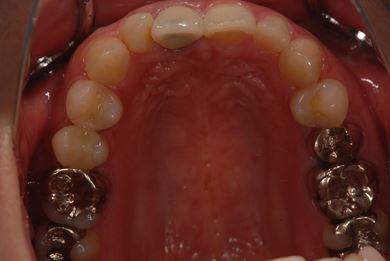

| 性別/年齢 | 女性 / 38歳 | ||||||||||||||||||||||||||||||||

| 主訴 | 右奥歯2本、インレーの相談をしたい。 | ||||||||||||||||||||||||||||||||

| 治療方針 | セラミック治療にて、審美的回復を行う。 | ||||||||||||||||||||||||||||||||

| 治療内容 | ハイブリッドセラミックインレー2本、メタルボンドセラミッククラウン2本(メタルボンド用土台2本)、オールセラミッククラウン1本(オールセラミック用土台1本) | ||||||||||||||||||||||||||||||||

| 総治療費 | 495,758円 | ||||||||||||||||||||||||||||||||

| 治療期間 | 1年6ヶ月 |